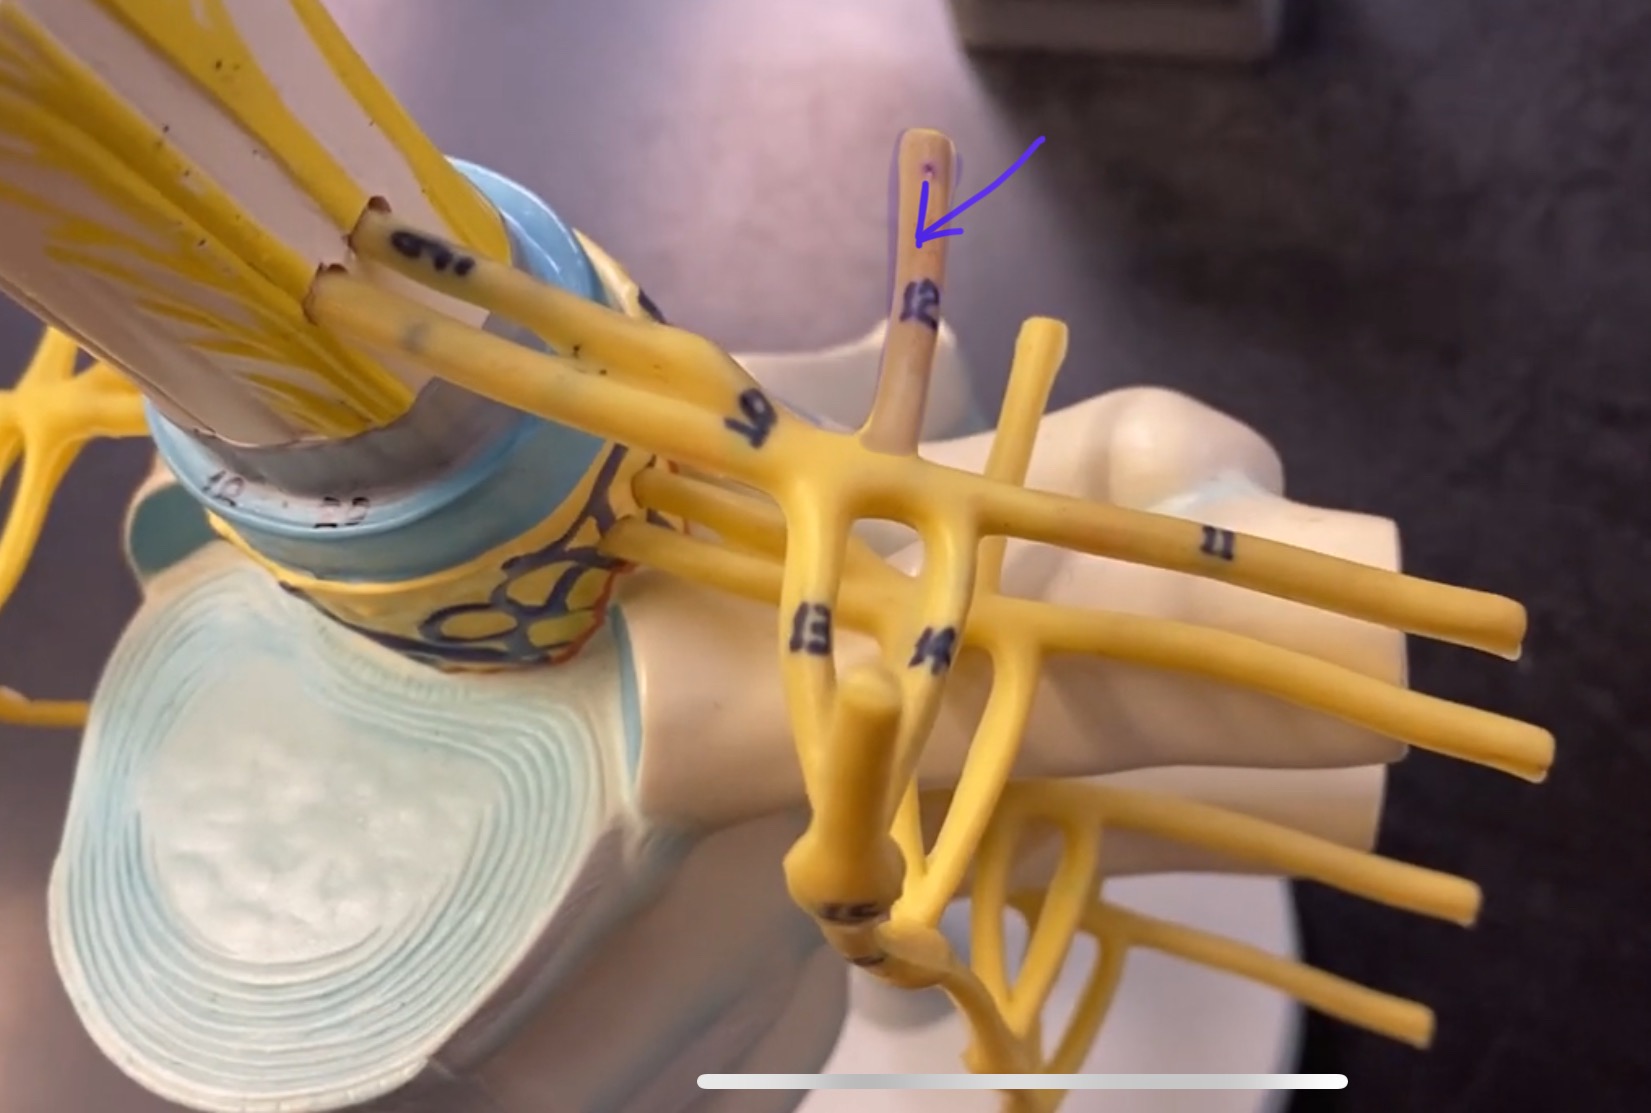

cervical enlargement

cervical enlargement

thoracic segment

lumbar enlargement

lumbar enlargement

conus medullaris

conus medullaris

filum terminale

cauda equina

sympathetic chain ganglia

posterior (dorsal) root ganglion

What is the bulb here?

posterior (dorsal) root ganglion

posterior (dorsal) root

posterior (dorsal) root

anterior (ventral) root

anterior (ventral) root

dorsal ramus

dorsal ramus

ventral ramus

ventral ramus

rami communicantes

rami communicantes

sympathetic chain ganglia

sympathetic chain ganglia